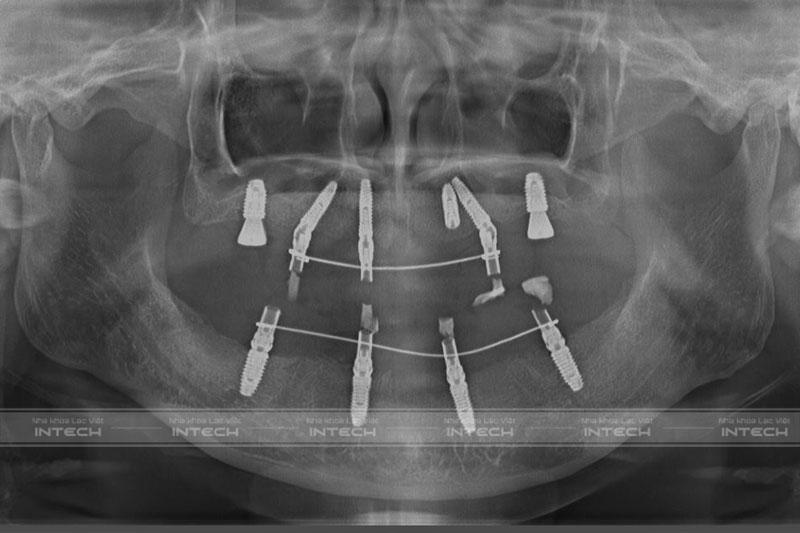

Sau khi thăm khám và chụp phim CT Conebeam, bác sĩ đã lên phác đồ điều trị cho cô Thủy. Bác sĩ Duy phân tích: “Với tình trạng này, giải pháp chúng tôi đưa ra cho cô Thủy đó là cấy ghép 6 trụ Implant để nâng đỡ, phục hồi lại toàn bộ hàm trên. Đồng thời nhổ bỏ các răng lung lay, không còn khả năng ăn nhai ở hàm dưới kết hợp cấy ghép 4 trụ Implant để nâng đỡ hàm dưới”.

Hình ảnh phim chụp X-quang sau khi cấy Implant của cô ThủyHình ảnh phim chụp X-quang sau khi cấy Implant của cô Thủy

Quá trình phẫu thuật cấy ghép Implant của cô Thủy diễn ra theo đúng như kế hoạch điều trị ban đầu. Các trụ Implant được cấy vào xương hàm chính xác, đảm bảo độ chắc chắn, ổn định và về nhà cô Thủy có thể ăn nhai nhẹ nhàng với hàm tạm.